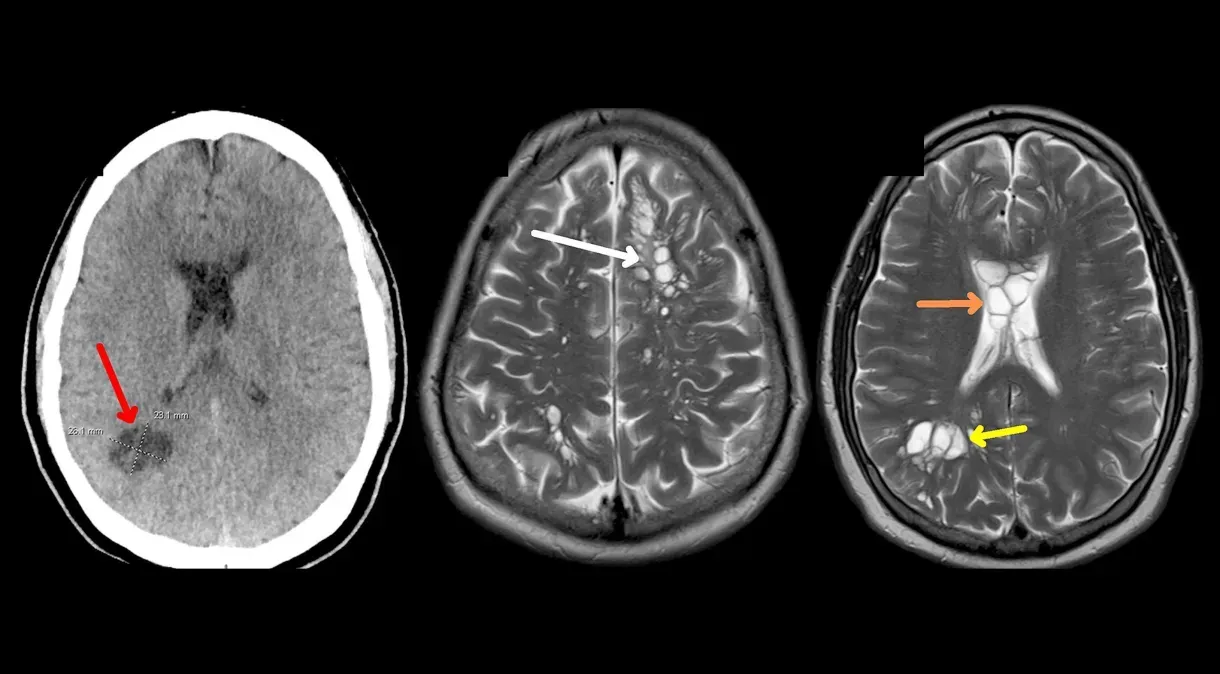

O médico pediu uma tomografia computadorizada, que mostrou múltiplos cistos – sacos cheios de líquido – em todo o seu cérebro. Suspeitando inicialmente que ele poderia ter uma rara condição neurológica chamada cistos neurogliais congênitos, os médicos o internaram em um hospital em Orlando para consultar um neurocirurgião.

Outros exames laboratoriais e de imagem no hospital mostraram que os cistos eram larvas parasitárias de tênia que haviam se estabelecido em seu cérebro e causado uma infecção chamada neurocisticercose, segundo o relatório.